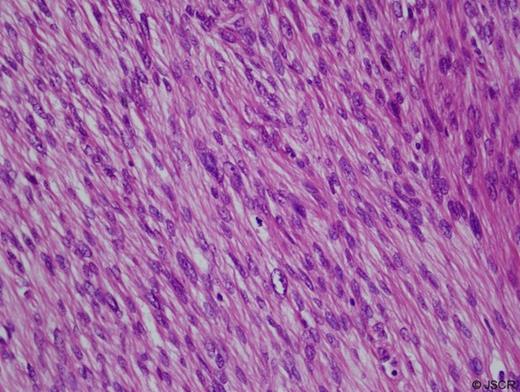

A 44 year old female patient presented to the surgical team with a firm lump in her left breast. The lesion had been present for three months when ultrasonography was performed, which found a lobulated tumor 3.5 cm in diameter in the lower in quadrant of her left breast. It was a hypoechoic and heterogeneous mass with an irregular shape, rough border and an irregular boundary echo. Fine needle aspiration biopsy was performed and was inconclusive. After discussion the multidisciplinary team decided that the patient should undergo excisional biopsy. A lumpectomy of the left breast was carried out. The subsequent histological diagnosis was stromal sarcoma with leiomyosarcomatous pattern. Microscopically, the tumor resected with mastectomy was a hypercellular nodule, and was composed of pleomorphic and hyperchromatic spindle-shaped cells arranged in an interdigitating fascicle (The tumors were circumscribed microscopically and were mild hypercellular nodules. Their nuclei were spindle shaped and showed mild to moderate atypia. Few mitoses were seen, and the surgical margins were free of tumor cells (Fig 1).

Microphotograph of leiomyosarcoma. Hematoxylin and eosin stain demonstrates a highly cellular, pleomorphic, and spindle shaped tumor with few mitotic figures (400×).